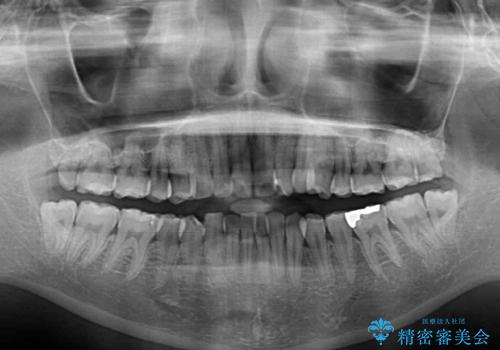

前歯のデコボコはもちろん気になるところですが、舌の突出癖により上下の前歯に大きな隙間がある状態でした。

上下前歯が非接触である開咬は、インビザラインによる治療がお勧めではありますが、非抜歯矯正か抜歯矯正か悩む口元であり、途中抜歯矯正に切り替えたときに対応しやすいよう、ワイヤー装置にて治療を行うこととしました。

舌の突出癖の影響もあり、非抜歯矯正で治療開始したものの口元が突出し、唇が閉じにくくなってしまったため、途中で第一小臼歯4本を抜歯ししました。